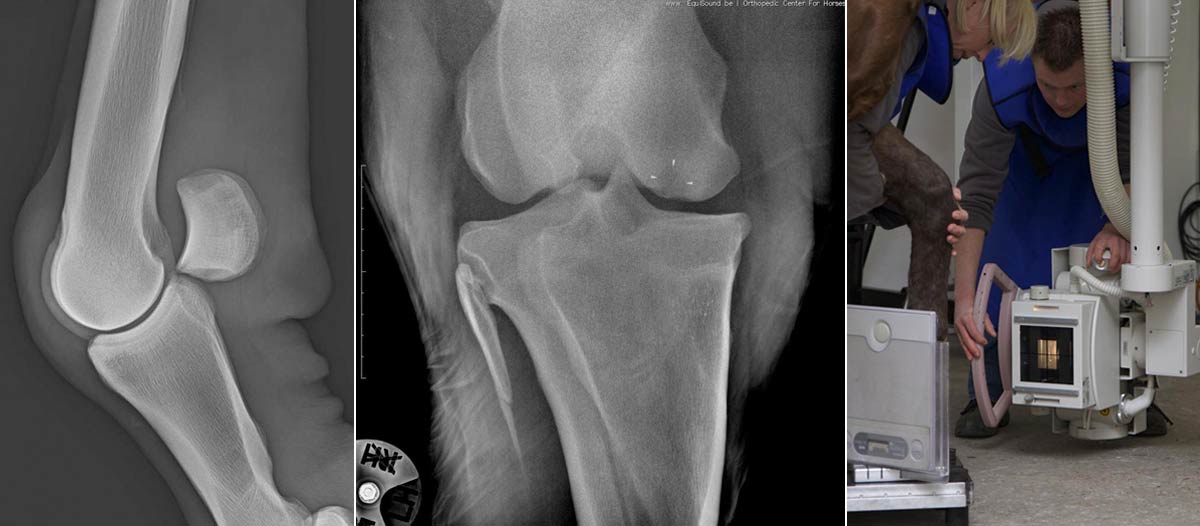

Radiologie

Radiologie bestaat al lang, maar toch blijft de technologie evolueren. EquiSound beschikt over digitale radiografie, gecombineerd met een röntgenbuis van 80.000 Watt (80kV). Zo maken wij kwalitatieve beelden van het volledige paard, inclusief nek, rug en hoofd.

Bucky Systeem

Info volgt